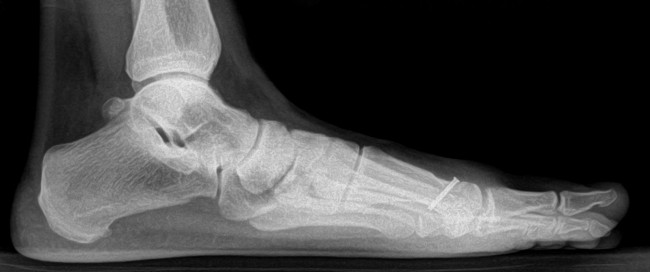

Prevalence of Vitamin D Deficiency in Patients With Foot and Ankle Injuries

Background: Vitamin D deficiency has been identified as one of the most common causes of fragility fractures and poor fracture healing.

Although rates of vitamin D deficiency have been delineated in various orthopaedic populations, little is known about the prevalence of vitamin D deficiency in patients with foot and ankle disorders.

The goal of this study was to identify the prevalence of vitamin D deficiency in patients with a low energy fracture of the foot or ankle.

Methods: Over a 6-month period, a serum 25-OH vitamin D level was obtained from consecutive patients with a low energy ankle fracture, fifth metatarsal base fracture, or stress fracture of the foot or ankle. For comparative purposes, vitamin D levels in patients with an ankle sprain and no fracture were also examined.

Results: The study cohort included 75 patients, of which 21 had an ankle fracture, 23 had a fifth metatarsal base fracture, and 31 had a stress fracture.

The mean age was 52 (range, 16–80) years.

Thirty-five of the fracture patients (47%) had an insufficient vitamin D level (below the recommended level of 30 ng/mL), and

10 of the patients (13%) had a level that was deficient (< 20 ng/mL).

Vitamin D levels were significantly lower in those with a fracture than in those with an ankle sprain (P = .02).

In the fracture cohort, the factors significantly associated with vitamin D insufficiency in the multivariate analysis were

smoking (P = .03),

obesity (P = .003), and

other medical risk factors for vitamin D deficiency (P = .03).

Conclusion: Hypovitaminosis D was common among patients with a foot or ankle injury seen at our institution. Patients with a low energy fracture of the foot or ankle were at particular risk for low vitamin D, especially if they smoked, were obese, or had other medical risk factors. Given that supplementation with vitamin D (± calcium) has been shown to reduce the risk of fragility fractures and improve fracture healing, monitoring of 25-OH vitamin D and supplementation should be considered in patients with fractures.